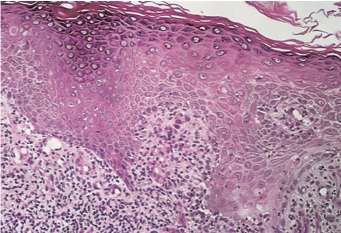

what are lichenoid basal layer damage conditions characterised by

damage between dermis and epidermis

lichen planus histology